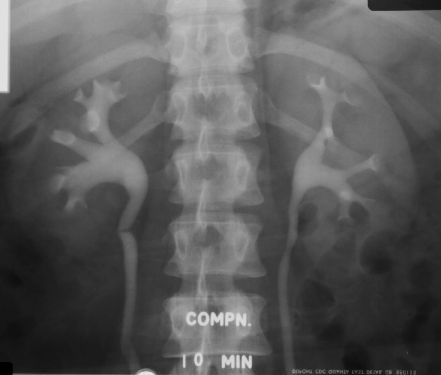

- IVP, MCU, ASU

- Certain X-Rays like lumbar spine, KUB require patient to come with empty stomach.